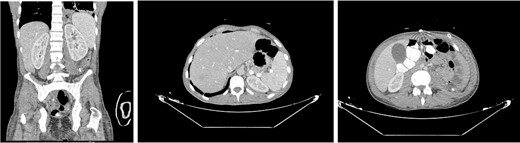

The patient was then admitted to the General Surgery department and treatment with broad-spectrum antibiotics (piperacillin/tazobactam, vancomycin, and metronidazole) was initiated. On the second day of hospitalization, the patient was led to the operating room, where the retroperitoneal cavity was exposed through a midline incision and a large amount of pus was drained. The retroperitoneal and peritoneal cavities were thoroughly irrigated, and three vacuum drains were placed. A pus culture was also obtained. On the fourth postoperative day, a new CT scan (Fig. 2) was performed, which revealed a significant decrease of the abscess as well as a significant reduction of the free fluids in the retroperitoneal area. Our patient showed a gradual clinical and laboratory improvement, and he was discharged on the eighth postoperative day. At the follow-up (3 months later), the patient’s overall health was satisfactory with no signs of a recurrence of the retroperitoneal abscess.

Postoperative CT done on the fourth day after surgery revealed a significant reduction in abcess size and improvement of the left lower lung lobe infiltration.